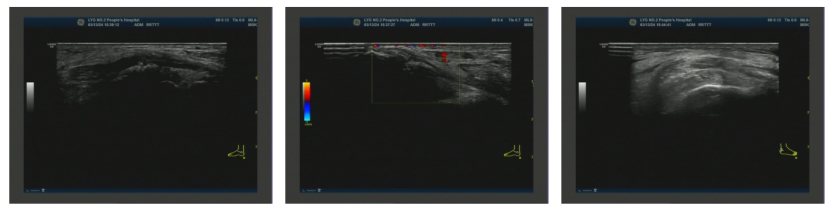

图4. 左侧腕关节浅表超声2025-01-21 右膝关节浅表超声:右侧膝关节积液;右侧膝关节滑膜炎伴痛风石形成,可见骨侵蚀;右侧股四头肌腱内强回声(痛风石?);右小腿软组织水肿(图5)。

图5.右膝关节浅表超声2025-08-16 第一跖趾关节浅表超声:双侧第一跖趾关节滑膜增厚伴痛风结晶形成(静止期)(图6)。

图6. 第一跖趾关节浅表超声2025-08-16 心脏超声:左房增大;室间隔增厚;主动脉瓣、二尖瓣、三尖瓣少量反流;左室舒张功能减低(图7)。